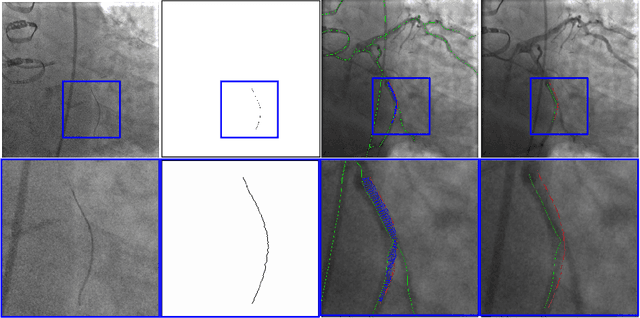

Abstract:In this article, we present the work towards improving the overall workflow of the Percutaneous Coronary Interventions (PCI) procedures by capacitating the imaging instruments to precisely monitor the steps of the procedure. In the long term, such capabilities can be used to optimize the image acquisition to reduce the amount of dose or contrast media employed during the procedure. We present the automatic VOIDD algorithm to detect the vessel of intervention which is going to be treated during the procedure by combining information from the vessel image with contrast agent injection and images acquired during guidewire tip navigation. Due to the robust guidewire tip segmentation method, this algorithm is also able to automatically detect the sequence corresponding to guidewire navigation. We present an evaluation methodology which characterizes the correctness of the guide wire tip detection and correct identification of the vessel navigated during the procedure. On a dataset of 2213 images from 8 sequences of 4 patients, VOIDD identifies vessel-of-intervention with accuracy in the range of 88% or above and absence of tip with accuracy in range of 98% or above depending on the test case.